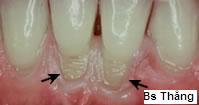

![]() | Mòn cổ răng do chải răng |

| | Mòn cổ răng ở mức nặng, rãnh mòn thông với buồng tủy gây nhiễm trùng tủy răng. |